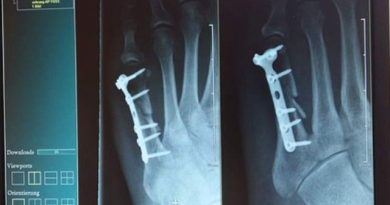

Saiba Tudo Sobre Fraturas E Como Fazer Os Primeiros Socorros O Que É Uma Fratura (Osso Quebrado)? Uma fratura acontece